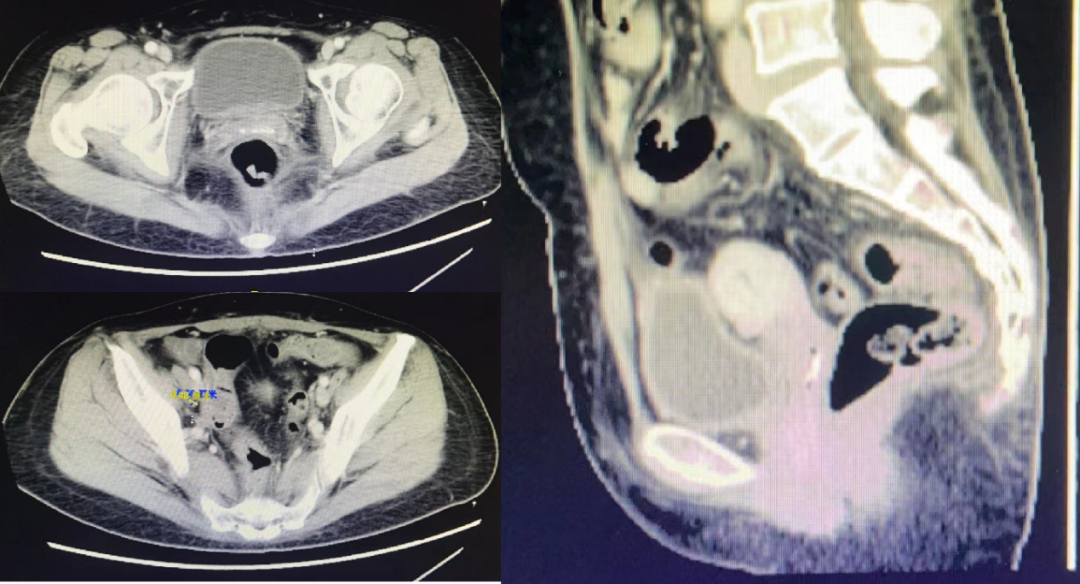

CT检查:发现宫颈巨大肿块,长径7.5公分。

9

图3. CT结果发现宫颈巨大肿块

CT影像学检查(2022年8月1日):肿瘤完全消退,转移性淋巴结明显缩小。

17

图10. CT结果显示肿瘤完全消退